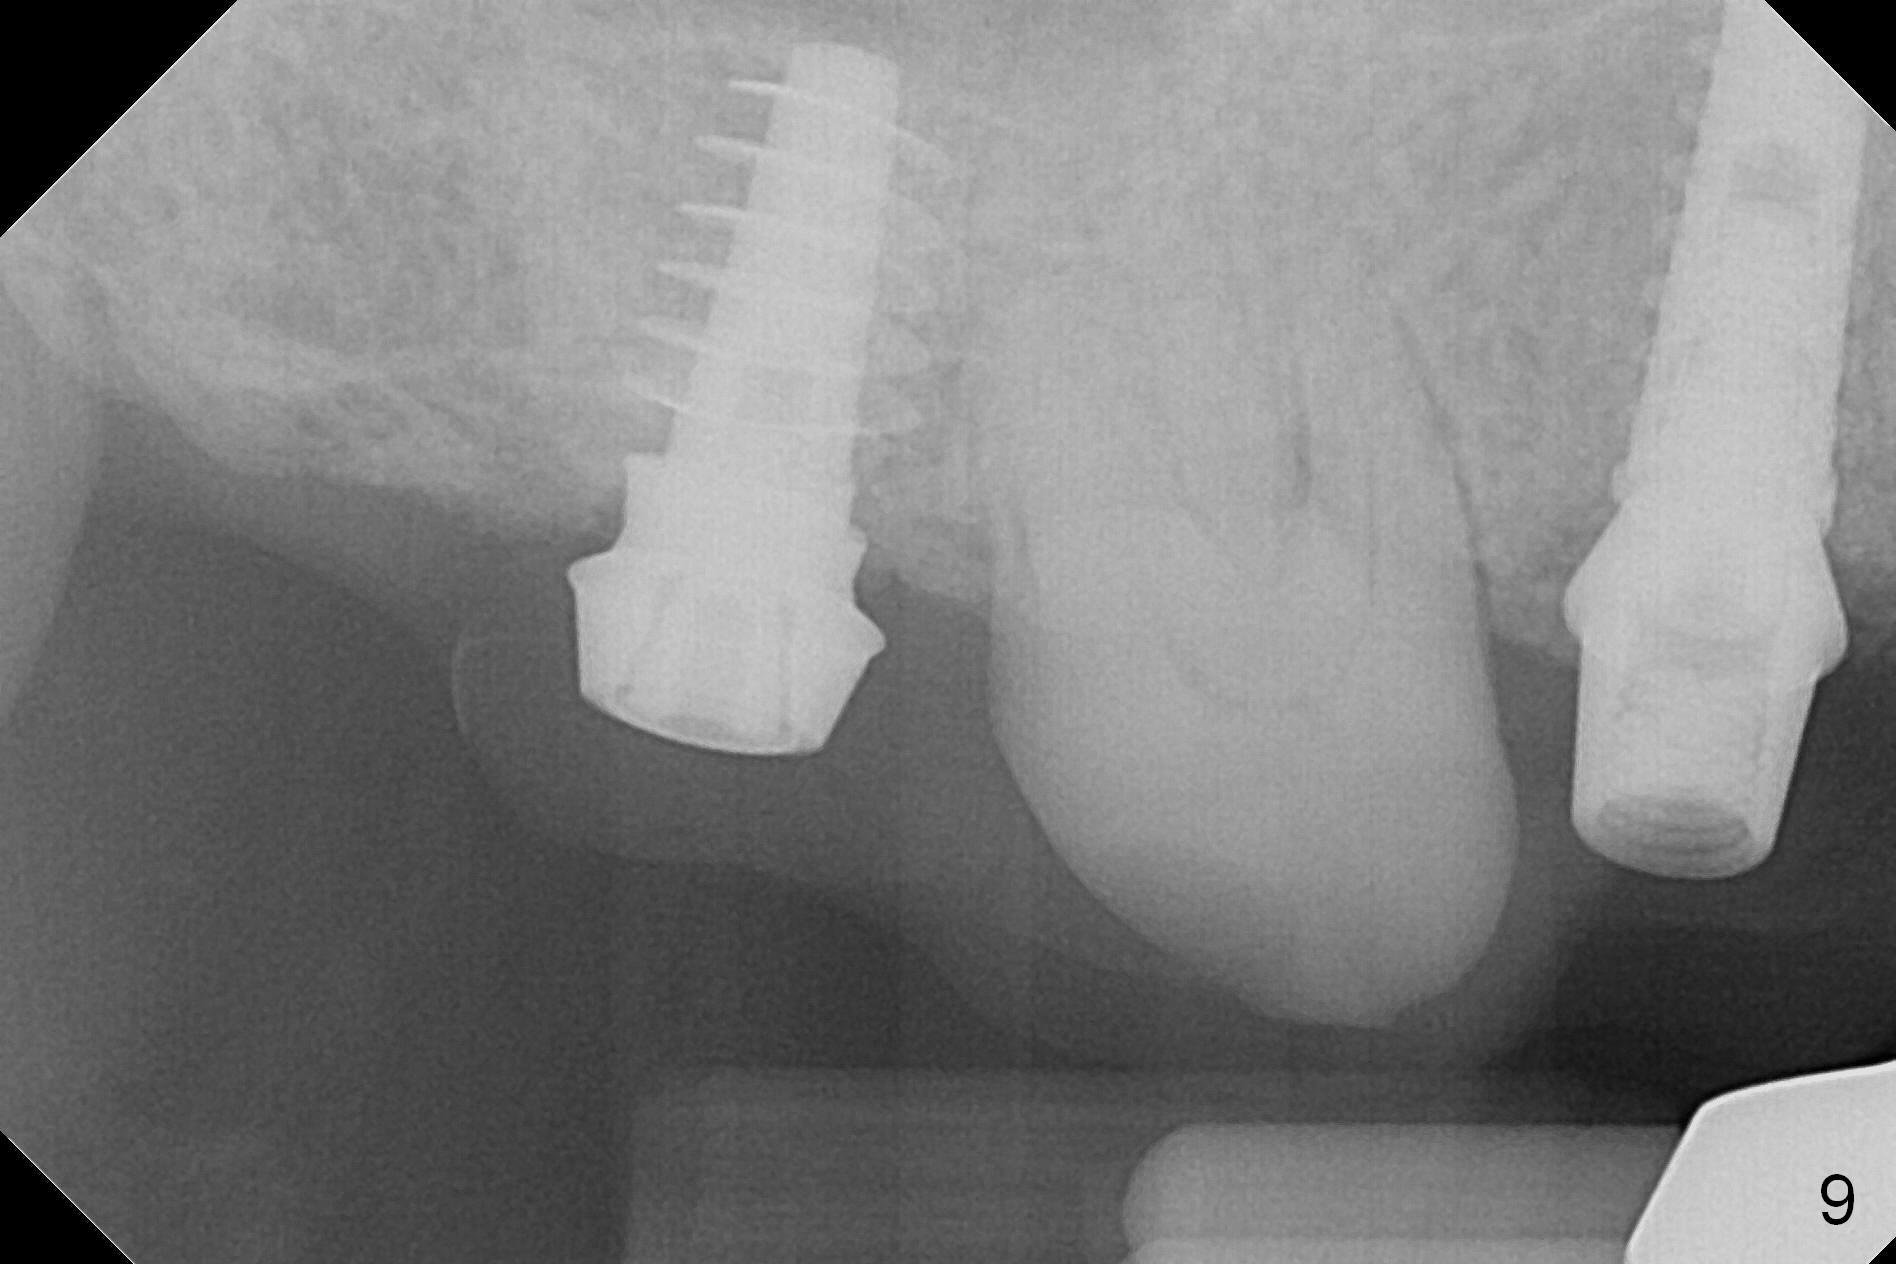

Preop exam shows posterior occlusal collapse (Fig.1) with #3 lost crown and #4 residual root. There is no ridge atrophy at #2 buccopalatally (Fig.2). The root stump of the tooth #4 is oblong, apparently consisting of 2 roots (Fig.3). There is a pointed septum at #4 socket (Fig.4, severe palatal wear of the anterior teeth (^)). After the septum is flattened with surgical handpiece and #8 round bur, 1.6 mm drill is used to start osteotomy in the septum, followed by Magic Drills (MD) and Magic Expanders (ME) alternatively. Osteotomy at #2 is initiated with Magic split, followed by MD and ME in the same manner. Dummy implants are tried in (Fig.5). Because of limited vertical height, Magicore (5.5x9(1) mm) is placed at #2, while a 4x13 mm FC implant 1-2 mm deeper than usual at #4 (Fig.6, ~ 55 Ncm). When a 5x4(2) mm pair abutment is placed at #4, there is no clearance between the Magicore at #2 and the abutment and the opposing dentition. A splinted provisional is fabricated at #3 and 4 to increase the posterior vertical height (Fig.7 P,8). In fact the occlusal contact is confined to the portion of the provisional at #3. The provisional has to extend to #4 to keep bone graft (Fig.6 *) and collagen plug in place. Liquid food is recommended at least 2-3 weeks, since there is no functional occlusal contact on the left. When the wound heals at #4 approximately 2-3 weeks, the splinted provisional can be sectioned with removal the portion at #4 to reduce micro-movement. By the evening the patient is doing well without nasal hemorrhage (sinus lift at #2 (Fig.6 *) or TMJ disturbance (due to increased vertical height).

In fact the upper provisional has been extended to cover #2-4 three months postop. When the patient returns again, it is approximately 4 months postop for #2 and 4 (Fig.9,10) and 3 months for #28. Reline or make the provisional so that the teeth #5 and 29 will be intruded (Fig.11 preop pan for comparision). The tooth #30 appears to have been intruded for the past 4 months. The provisional at #3 is short so that the tooth #30 may be able to erupt (Fig.12).